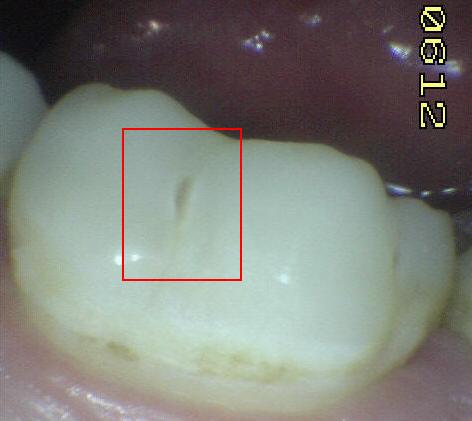

Código 4

(Caries Moderada): Sombra oscura

de dentina

subyacente al esmalte intacto con o sin interrupción localizada del

esmalte

- Esta lesión aparece como una sombra de

decoloración visible a través de una cresta marginal,

aparentemente intacta, o con pequeña micro-cavidad o perdida

de continuidad del esmalte, después del secado con aire por

5 segundos.. Las paredes vestibular o lingual

del esmalte dejan traslucir dentina decolorada.

Este aspecto se ve a menudo con más facilidad cuando el

diente está húmedo. El área oscura es una sombra intrínseca

que puede aparecer como gris, negro-azul o marrón-anaranjado

- Puede utilizarse

una sonda periodontal para identificar

la micro-cavidad en esmalte o discontinuidad < 0,5 mm.